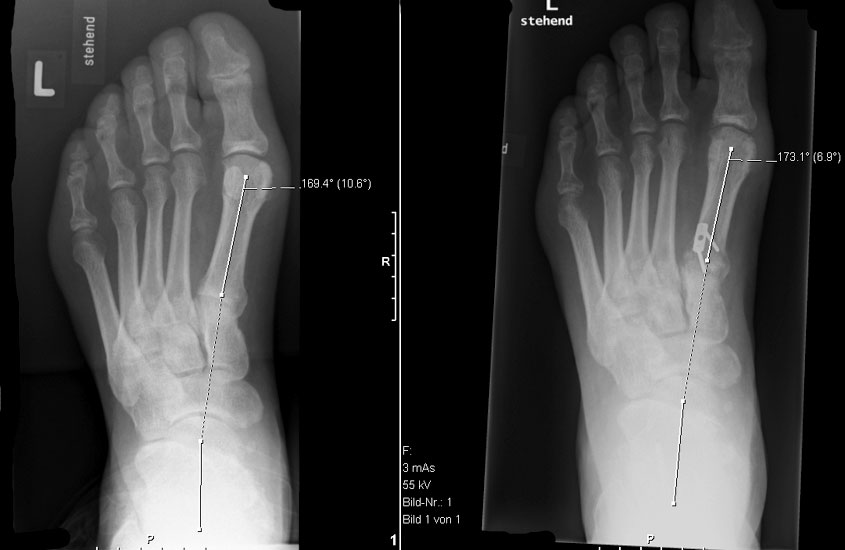

Peroneus longus auf brevis Transfer (Abb. 4 und 5, Video 3)

• Plantarflektiertes Metatarsale I (lateraler Talo-MT I Winkel mehr als 10°) und schwacher M. peroneus brevis (lateraler Rückfuβ-Instabilität).

Dorsalflektierende Osteotomien des medialen Mittelfuβes (Abb. 6 – 9, Video 4)

• Erhöhter lateraler Talo-Metatarsale I Winkel (Meary-Winkel) als Ausdruck des plantarflektierten medialen Mittelfuβes, insbesondere im "forefoot driven hindfoot varus" (positiver Coleman block Test).

Generell wird die dorsalflektierende MT I Osteotomie (Abb. 6 und 7) nicht isoliert ausgeführt, sondern ist Teil der gesamten Hohlfuβ-Korrektur. Beim absolut flexiblen Hohlfuβ ist sie gelegentlich zusammen mit einem Peroneus longus auf brevis oder einem Release der Plantarfaszie ausreichend. Diese Osteotomie ist einfach durchzuführen und hat eine geringe Pseudarthroserate.